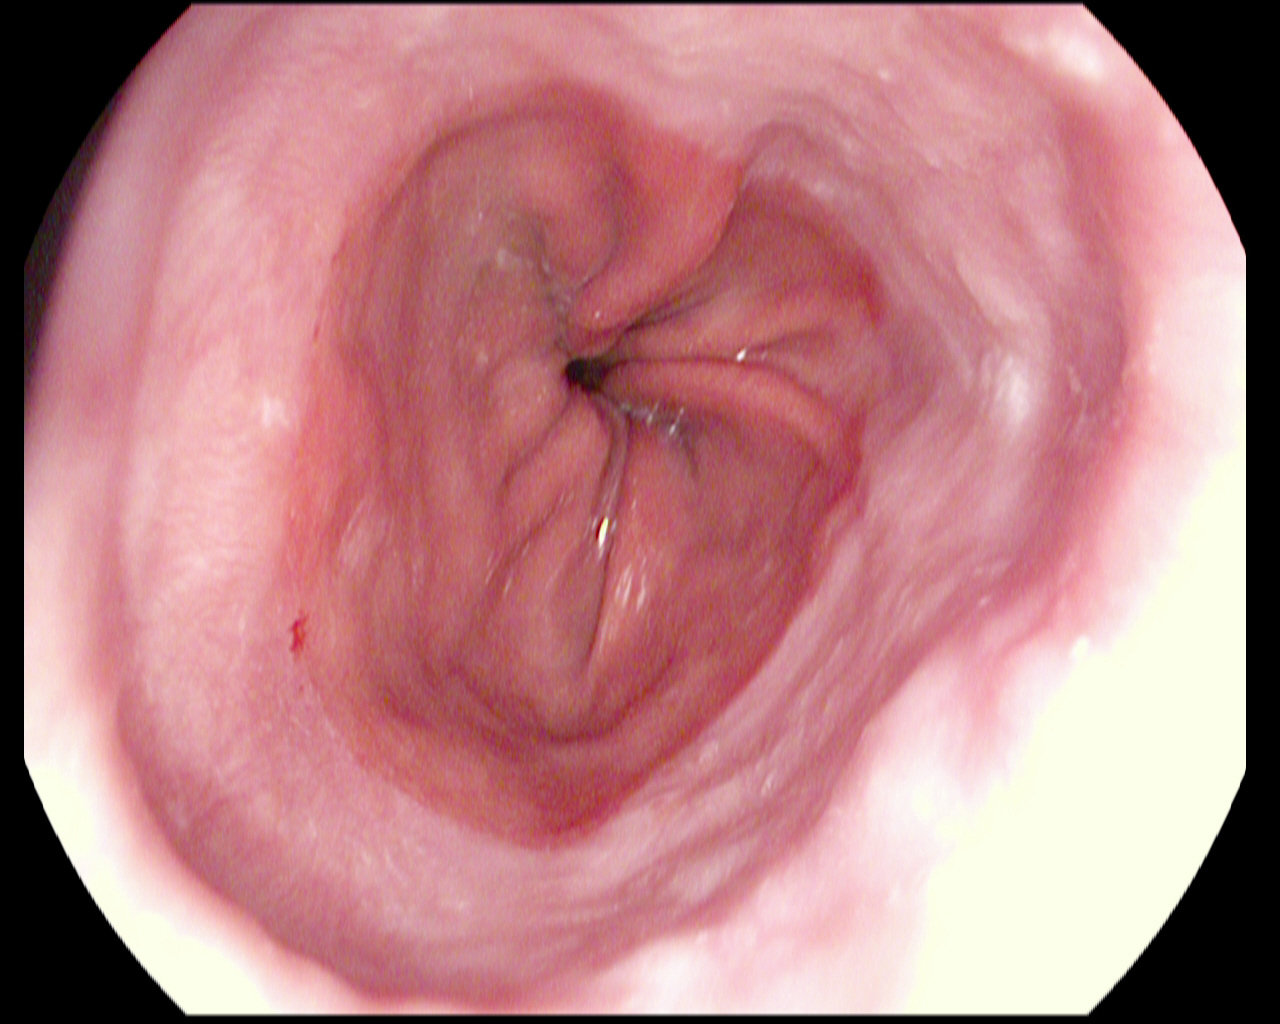

Polyps

Ulcerative colitis

Normal cecum

Esophagitis

Normal z-line

Normal pylorus